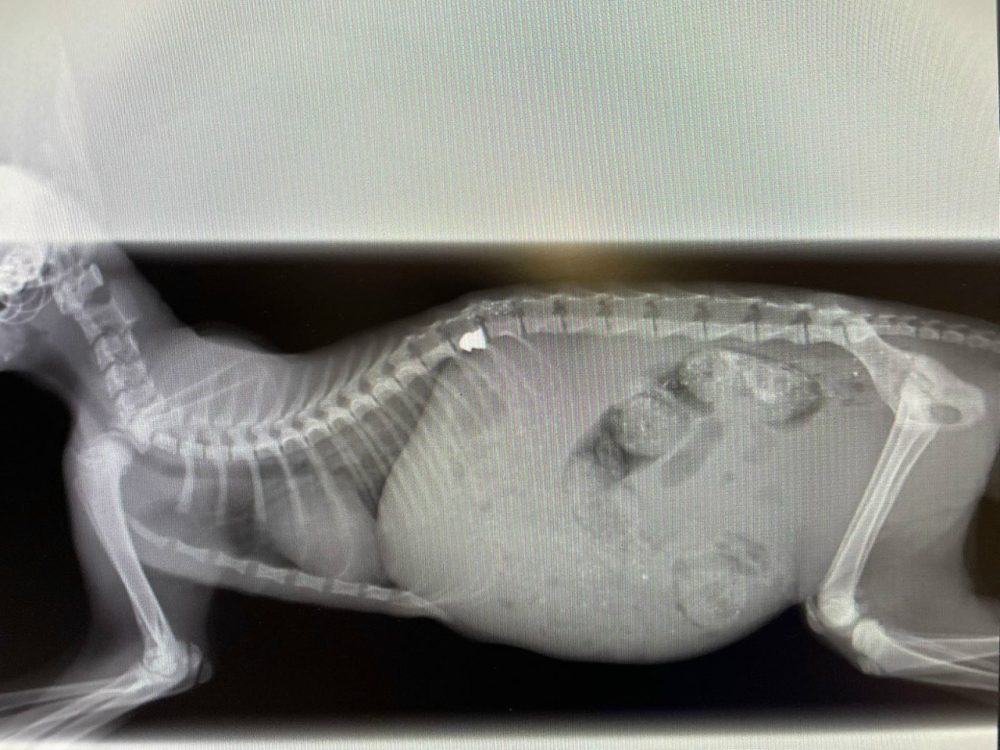

Таццяна патэлефанавала валанцёрцы Маргарыце, якая адразу пагадзілася забраць кацяня. На наступны дзень тая адвезла яго ў мінскую клініку «Доктар Вет», дзе зрабілі МРТ і аперацыю па выманні кулі. Аднак у выніку стрэлу быў пашкоджаны пазваночнік, і заднія лапкі ў малога паралізаваныя.

Пяць дзён пасля паласной аперацыі кацяня знаходзілася ў стацыянары. Потым Маргарыта забрала яго дадому, абсталяваўшы яму асобнае месца. Малы атрымаў імя Ёсік. Стан у яго стабілізаваўся, ён стаў больш актыўны, але ветэрынары папярэджваюць: цалкам хадзіць ён, напэўна, ужо не зможа.